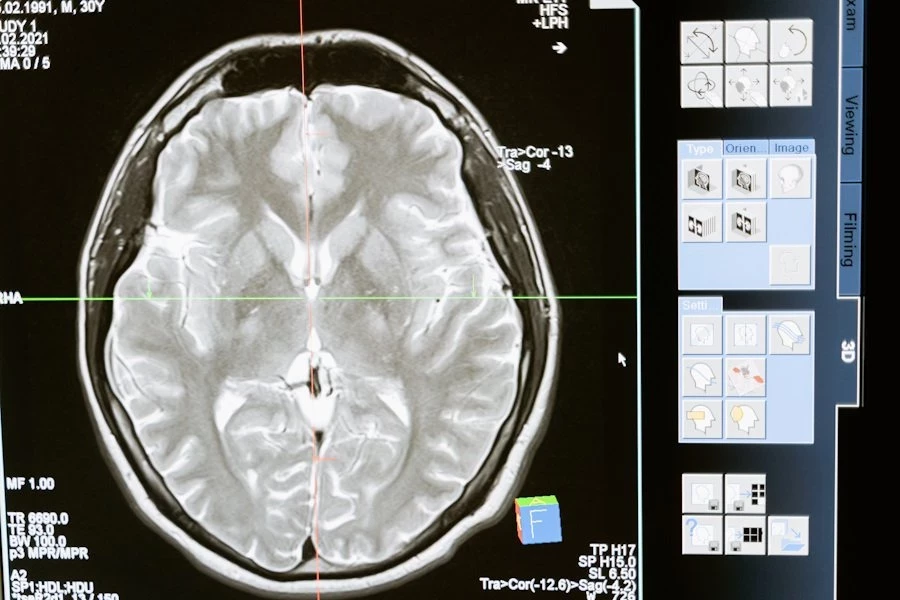

Как сон влияет на мозг: связь между апноэ и повреждением белого вещества

Исследователи из Университета Майами сделали важное открытие: проблемы с дыханием во время сна, такие как апноэ и гипопноэ, могут вызывать изменения в структуре мозга. Это открытие проливает свет на сложную связь между качеством сна, памятью и старением мозга. Работа опубликована в журнале Neurology.

В исследовании приняли участие 2 667 человек со средним возрастом 68 лет, преимущественно латиноамериканского происхождения. В рамках эксперимента они прошли домашнее тестирование сна, позволяющее зафиксировать остановки дыхания и замедления. На основе этих данных участников разделили на три группы: без нарушений дыхания, с лёгкими нарушениями и с тяжёлыми нарушениями. Через 10 лет все добровольцы прошли сканирование мозга.

Результаты анализа показали, что у людей с тяжёлыми нарушениями дыхания объём гиппокампа — области мозга, ответственной за память и мышление, — оказался на 0,24 кубического сантиметра больше, чем у тех, кто спал без проблем. Более того, каждое дополнительное нарушение дыхания приводило к увеличению объёма гиппокампа на 0,006 кубического сантиметра.

Ещё одна важная находка связана с уровнем кислорода в крови. Учёные выяснили, что снижение кислорода во время сна связано с увеличением гиппокампа и повреждением белого вещества мозга. Повреждённые области белого вещества, согласно исследованию, могут нарушать взаимодействие между различными участками мозга.